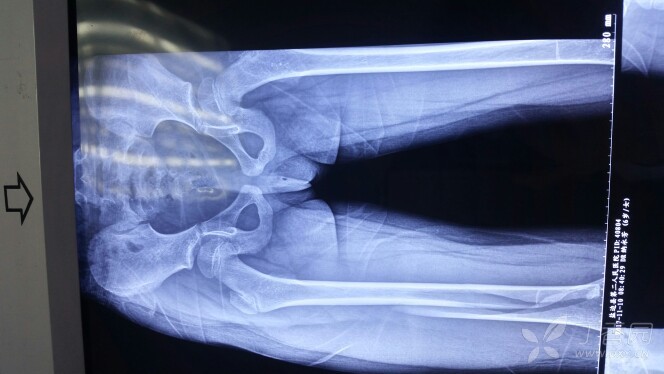

左股骨干骨折

图片尺寸960x1280